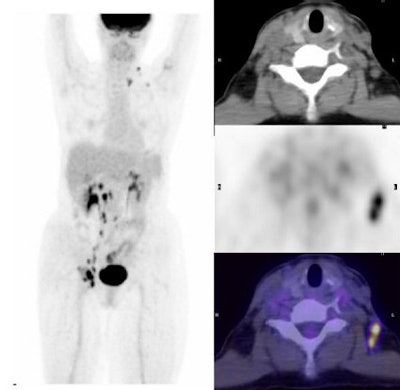

| Above and below, a 55-year-old woman with cervical carcinoma. Lymph node metastases are seen on the transaxial PET, CT, and fused PET/CT images. All images courtesy of Stanford University. |